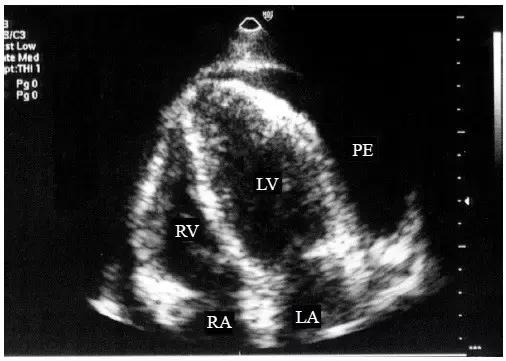

【中量心包积液】

左心室后壁心包腔内液体增多,心尖部也可探及液性暗区,但液性暗区不越过二尖瓣环,未抵达左心房的后方,右心室前壁液性暗区宽度<10mm(图2)。

图2 中量心包积液的二维超声心动图表现

左心室后壁和右心室前壁心包腔内均见液性暗区